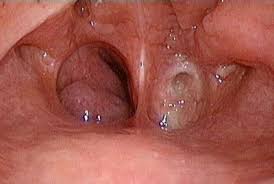

Папилломатоз гортани у детей: полное руководство для родителей по лечению

Столкнулись с диагнозом папилломатоз гортани у ребенка и ищете ответы. Наша статья подробно объясняет причины, симптомы, современные методы диагностики и эффективного лечения, чтобы вернуть ребенку здоровое…